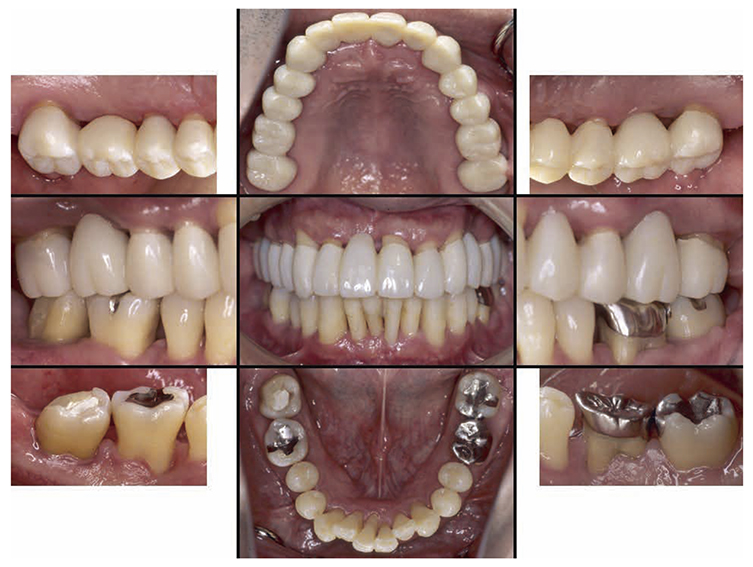

7) Reevaluation testing (December 2003)

At the reevaluation examination after treatment to restore oral function, the color of gingiva was pink, and with prosthetics, intraoral harmony was replicated esthetically and functionally. (Fig.6a). The average PD across the entire jaw was 2.1mm, maximum PD was 4.0mm, the ratio of PD of 3mm or below was 99.3%, no BOP was found and the condition of the periodontal tissue was stable (Fig.6b). In the X-ray, continuity of the alveolar hard line was replicated and the sequence of bone trabeculae was normal, and therefore, the patient transitioned to the SPT phase (Fig.6c).

Fig 6a

(Fig.6a) Intraoral photo after completion of restoration of oral function was completed(2013.4)

8)SPT (December 2013 onward)

After transitioning to SPT, the patient brushed 4 times daily after every meal and before bedtime and has continued to use an interdental brush. PCR levels have been consistently in the 20% range. SPT , which primarily consists of instructions on brushing and dental surface cleaning, has been implemented every other month to present, and efforts are made to maintain and manage oral hygiene in the long term to ensure that plaque control is not insufficient. While minor discoloring is observed on the prosthetics, the color of the gingiva is salmon pink and a macroscopically healthy appearance has been sustained (Fig.7a) . The average PD on the entire jaw is 2.1mm,maximum PD is 4.0mm,the ratio of PD of 3mm or less is 99.3%. No BOP has been found and the condition of the periodontal tissue has been stable (Fig.7b). In the X-ray, continuity of the alveolar hard line has been replicated and the sequence of the bone trabeculae has been normal (Fig.7c).

Fig 7a

(Fig.7a) Intraoral photo: 15 years after first visit (December 2022)